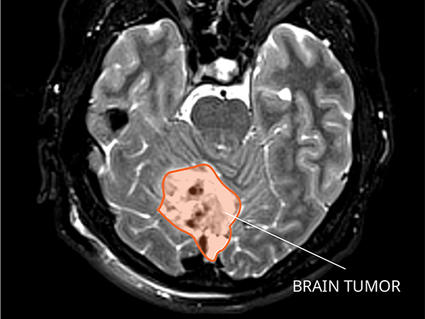

A new study in mice has shown that loading the cancer drug palbociclib (Ibrance) in nanoparticles can boost its ability to fight medulloblastoma, a type of brain cancer. The nanoparticle coating helps the drug reach tumors better and stay in the body longer, according to the researchers who led the study.

Medulloblastoma is a rare, aggressive brain cancer that affects children and young adults. While most patients are cured with surgery, radiation, and chemotherapy, they are typically left with debilitating side effects. And for the 1 in 5 people whose cancer comes back after initial therapy, there are no highly effective treatment options.